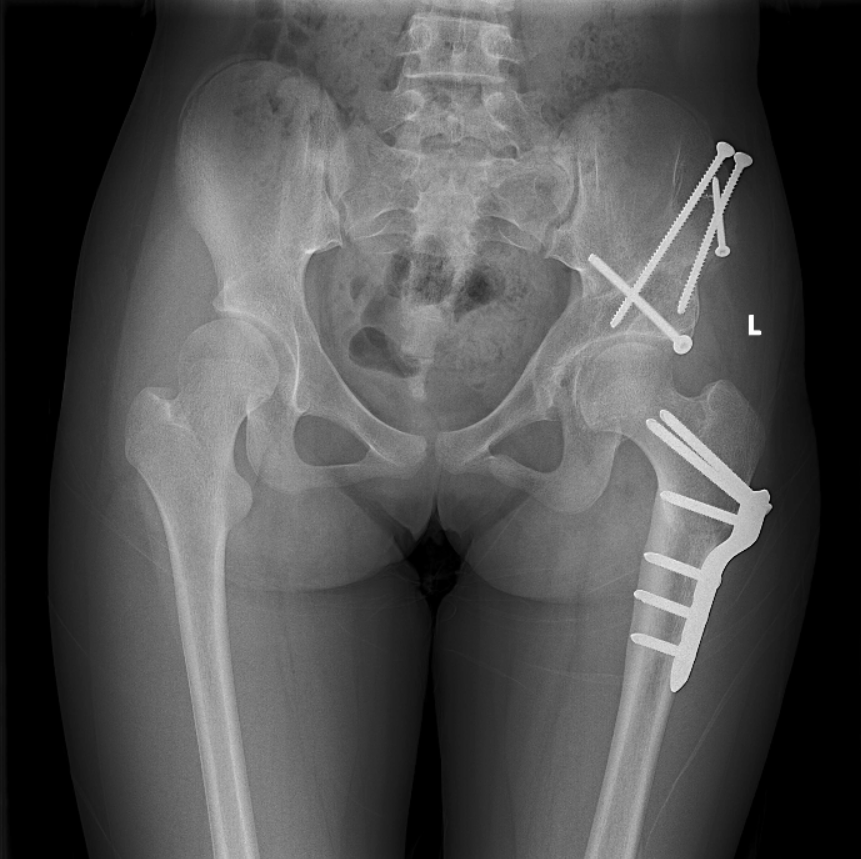

2021-01 左侧髋臼PAO截骨术后1年3月,右侧术后2年3个月:双髋关节正位X线片

2021-01 双侧髋臼PAO截骨取钉术后:双髋关节正位X线片